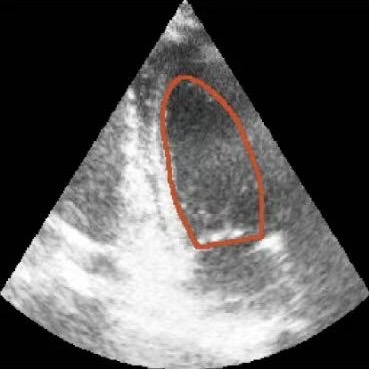

Figure 1: Illustrative challenges for echocardiography video segmentation: (a) speckle noise, (b) indistinct or blurred contours, and (c-f) the substantial changes in the target’s shape and scale throughout the cardiac cycle.

However, achieving precise segmentation in echocardiography faces severe challenges stemming from poor image quality and complex cardiac dynamics. Figures 1(a) and 1(b) show that ultrasound images are characterized by high speckle noise and low contrast, which obscure tissue structures and lead to weak or incomplete anatomical boundaries. These artifacts hinder the model’s ability to learn robust features and can result in the inaccurate segmentation. In the temporal dimension, the heart undergoes significant non-rigid deformation throughout the cardiac cycle. Figures 1(c), 1(d), 1(e) and 1(f) show that, the shape and scale of the LV change dramatically between systole and diastole. This substantial dynamic variation demands that segmentation models possess strong temporal modeling capabilities to accurately track the changing appearance of the target across the video sequence [20].